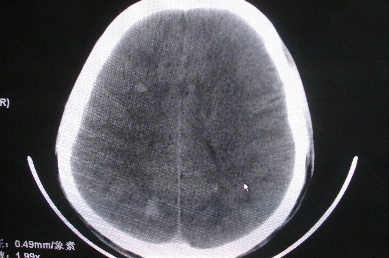

以下是引用zhangzhongshou在2007-4-18 17:49:00的发言:[br]脑实质内多发高密度结节影,支持肉芽肿得诊断,究竟是结核性、真菌性或寄生虫性的需结合临床,进一步检查确诊,但从影像上无法鉴别,只是临床上结核性肉芽肿最为多见而已。